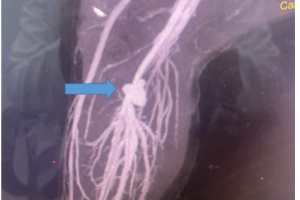

Vừa qua, bệnh viện Nhi đồng Thành phố, tiếp nhận một trường hợp trẻ Tr. P. A. 7 tuổi, nam, ngụ Sóc Trăng trong tình trạng khó thở, tím tái, được chuyển từ bệnh...